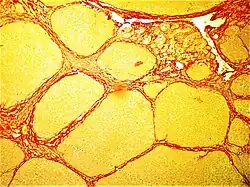

Micrograph of a heart showing fibrosis (yellow – left of image) and amyloid deposition (brown – right of image). Stained using Movat's stain.